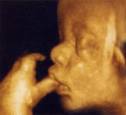

Gravidanza: l’ecografia 4D

L’ecografia 4D dà la possibilità di vedere meglio il bambino compresi i lineamenti e le espressioni del volto. Tutto questo grazie ad una tecnologia più avanzata fa si che il bambino si presenti in modo tridimensionale (altezza, lunghezze e profondità), con in più la dimensione del tempo, il che significa si riesce a vedere il bambino mentre si muove.

I particolari che si potranno vedere sono per esempio a chi assomiglia il bambino, se sta sorridendo, se sta sbadigliando, se muove le manine provando ad aprirle e chiuderle, se si sta succhiando il ditino, se sta giocherellando con il cordone ombelicale, se tira fuori la lingua.